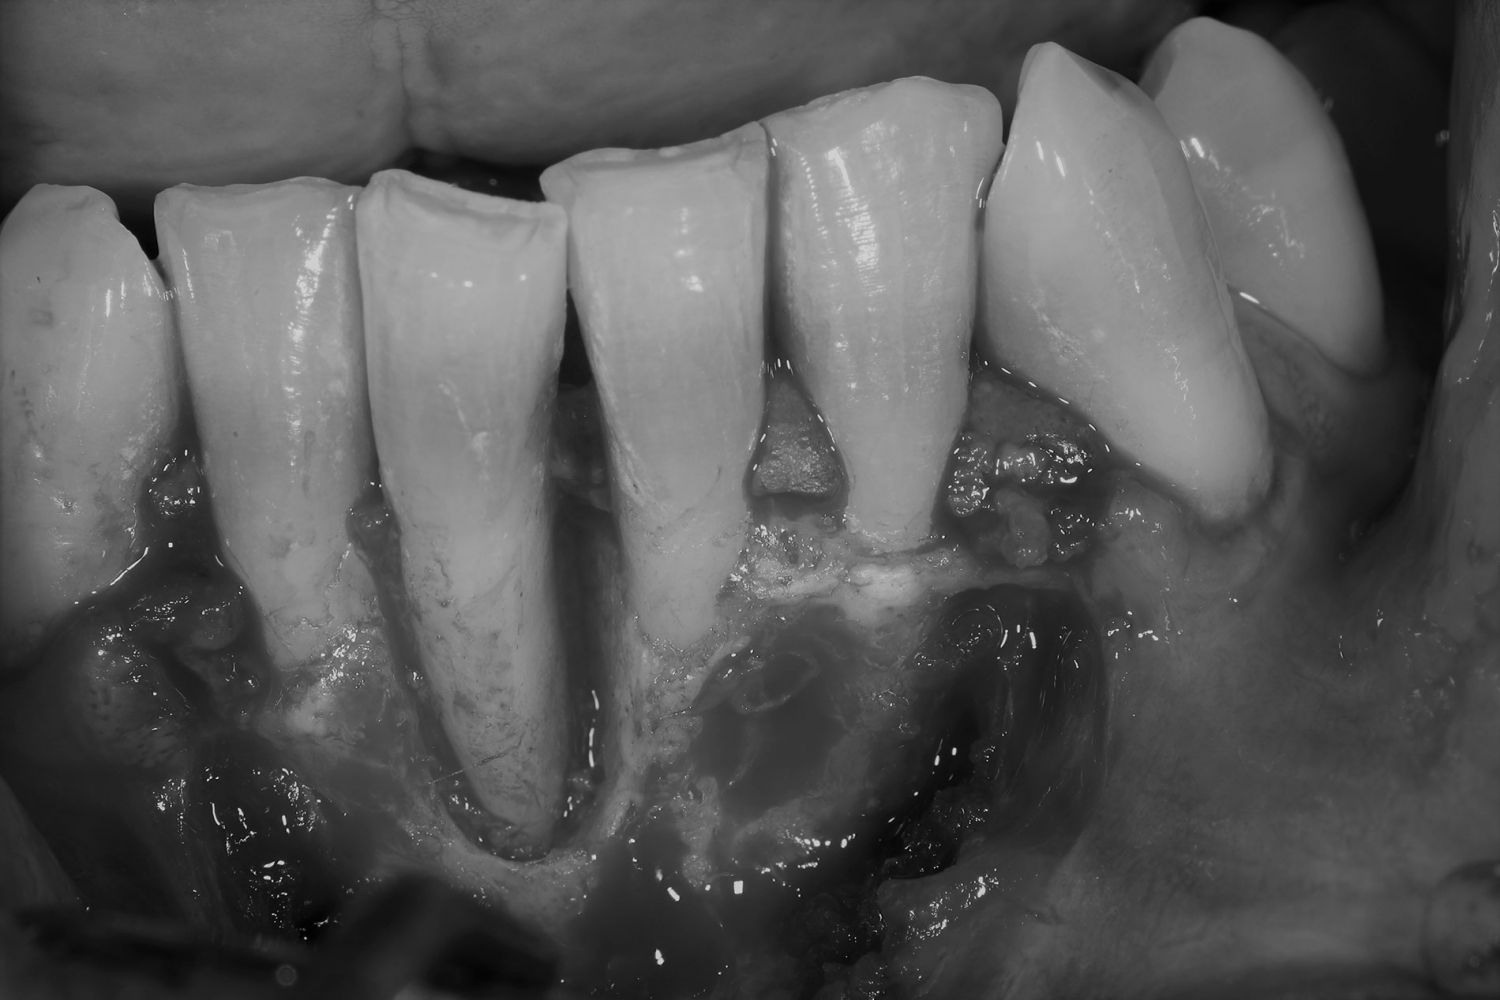

Caso de cirugía periodontal

Cirugía periodontal en un paciente